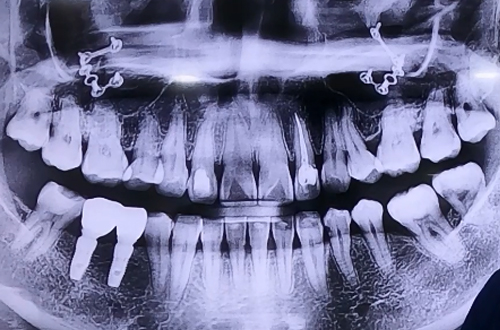

AFTER

오른쪽 아래 임플란트 보철을 완성하고 최근에는 왼쪽도 임플란트를

진행하면서 신경에 닿지 않도록 실시간으로 확인하며 진행해 드린 환자분이십니다.

수술시간은 다른 환자분들보다 조금 더 걸리는 수술이었지만 하치조 신경에

닿지 않고 안전하게 수술하는 게 가장 중요했던 케이스입니다.

임플란트를 심어드린 다음 잇몸뼈가 부족한 부분은 뼈이식을 통해 단단하게 마무리해 드렸습니다.

추후 임플란트 보철 머리 부분 올라가시게 되면

다음 진료일지로 찾아뵙도록 하겠습니다^^!